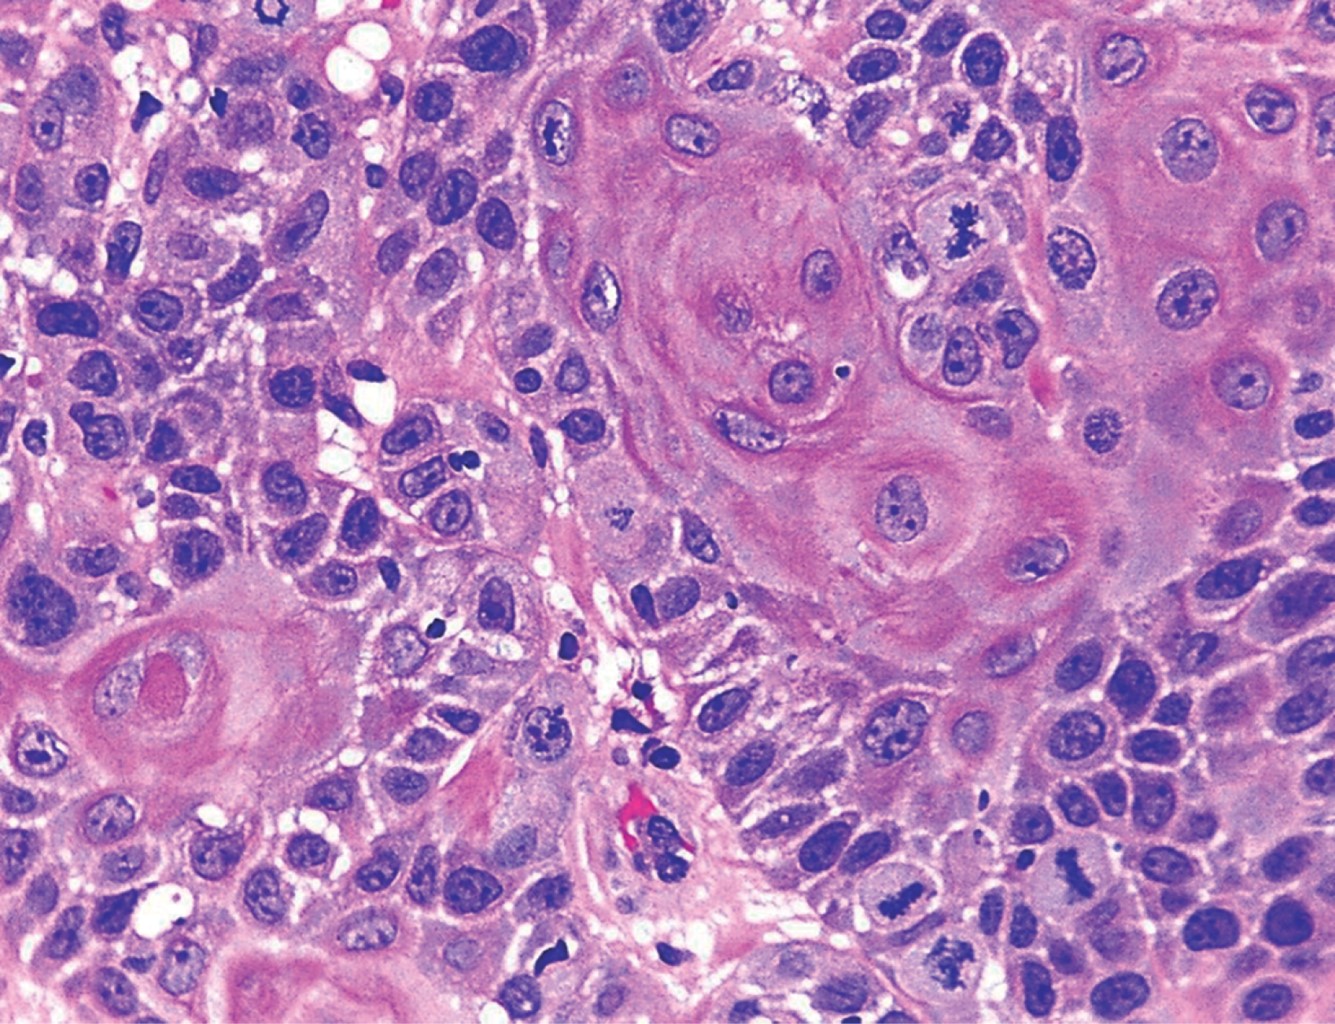

HISTOPATOLOGíA

Las imágenes histopatológicas muestran patrones de diferentes carcinomas cutáneos, principalmente de carcinoma epidermoide en 71%.3 El resto corresponde a carcinoma basocelular, melanoma, sarcoma, entre otros.1,3

Paciente del sexo masculino, de 43 años de edad, originario y residente de Guerrero, desempleado. Acude por una dermatosis localizada a tronco, del que afectaba tórax posterior en la región escapular izquierda; constituida por una neoformación exofítica, de 10 × 8 cm en su eje mayor, ulcerada, con costras melicéricas y secreción purulenta en su superficie, de bordes irregulares y bien definidos (Figura 1). Presentaba también una segunda neoformación en región escapular y hombro de lado izquierdo, de aspecto atrófico, de 9 cm de diámetro, con escama amarillenta y gruesa en su superficie, de bordes mal definidos (Figura 2), ambas de evolución crónica, dolorosas, que emitían olor fétido. Presentaba además adenopatías palpables ipsilaterales. Como antecedentes de importancia refirió haber sufrido una quemadura de tercer grado extensa en tórax y extremidades superiores con gasolina 22 años antes. El padecimiento actual lo inició hace tres años, con una "bola de rápido crecimiento" (sic paciente), la cual más tarde se ulceró en forma espontánea, acompañándose de sangrado y dolor progresivo. Acudió con especialista en Guerrero quien realizó biopsia y lo canalizó a este centro dermatológico con el diagnóstico de carcinoma epidermoide moderadamente diferenciado queratinizante, invasor (Figuras 3, 4 y 5). Al tratarse de un tumor de alto riesgo, el paciente fue referido a un hospital de tercer nivel en donde falleció al mes del internamiento debido a choque séptico y fascitis necrotizante.

Figura 5